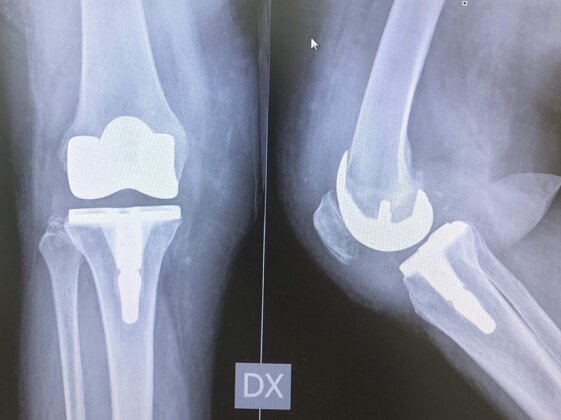

Radiografie post-operatorie in AP e LL di intervento chirurgico di protesi monocompartimentale mediale di ginocchio cementata. Questo tipo di protesi è utilizzabile in pazienti con artrosi localizzata in uno solo dei due compartimenti mediale o laterale e con integrità del LCA. Il recupero post-operatorio è più rapido rispetto ad una protesi totale di ginocchio